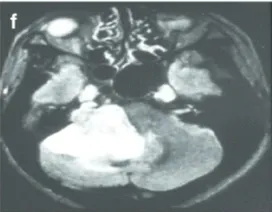

下图显示了放射治疗失败的其他病例,与这些患者相比,这些患者表现出更快的肿瘤再生长和更严重的临床症状(图3a–c)。由于脑干受压增加,这些病例都需要在伽玛刀治疗后3年内进行显微手术切除。图3d–f展示了立体定向放射治疗(SRT)之后的一些放射学变化。

f-42岁男性。FLAIR轴向磁共振成像显示右侧大肿瘤,伽马刀治疗后小脑明显受损